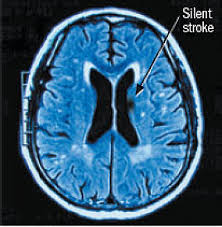

Silent Strokes: The 'Hidden Burden' on Your Brain

What are Silent Strokes?

Silent strokes, formally known as non-symptomatic strokes, are strokes that occur without the classic, immediately recognizable signs most associate with a stroke - like sudden weakness, slurred speech, or severe headaches. While these events often bypass our immediate awareness, they inflict damage on brain tissue, detectable through advanced neuroimaging techniques such as Magnetic Resonance Imaging (MRI). The insidious nature of silent strokes is that the effects might not manifest for years, gradually contributing to cognitive decline, memory impairment, and a variety of neurological issues. They represent a 'hidden burden' of brain injury impacting overall health and longevity.